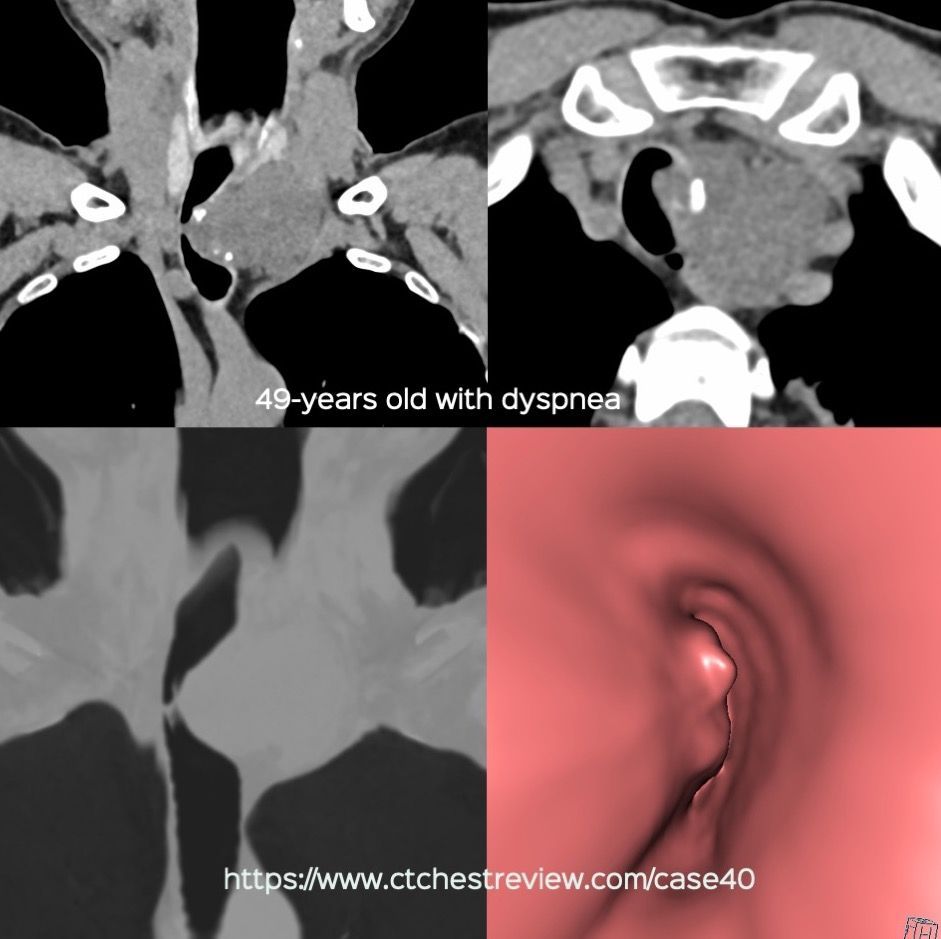

Case 40: Why is 2 + 2 Not Considered 4? Members Public

A mediastinal mass where 2 + 2 = 4